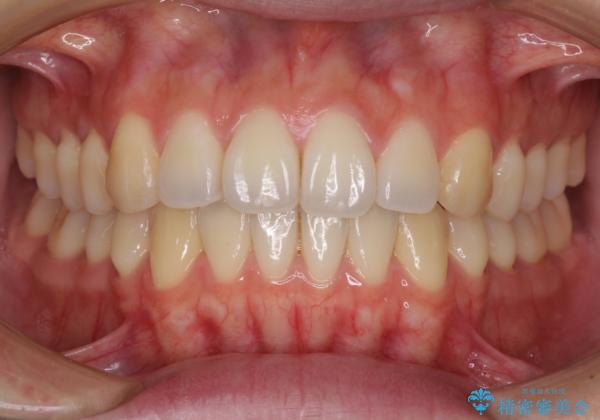

オープンバイトでかみにくい インビザラインによる矯正治療

- 前歯の上下スペースによる食べにくさを気にして来院された患者様です。

インビザラインにより上下の前歯の隙間を閉じていくこととしました。

上下の奥歯を圧下させるようにすることで、前歯を接触させるように計画しました。

上下の隙間に舌が入り込むことがオープンバイトの原因であったため、舌の筋肉のトレーニングも並行して行い、後戻りの抑制を図りました。